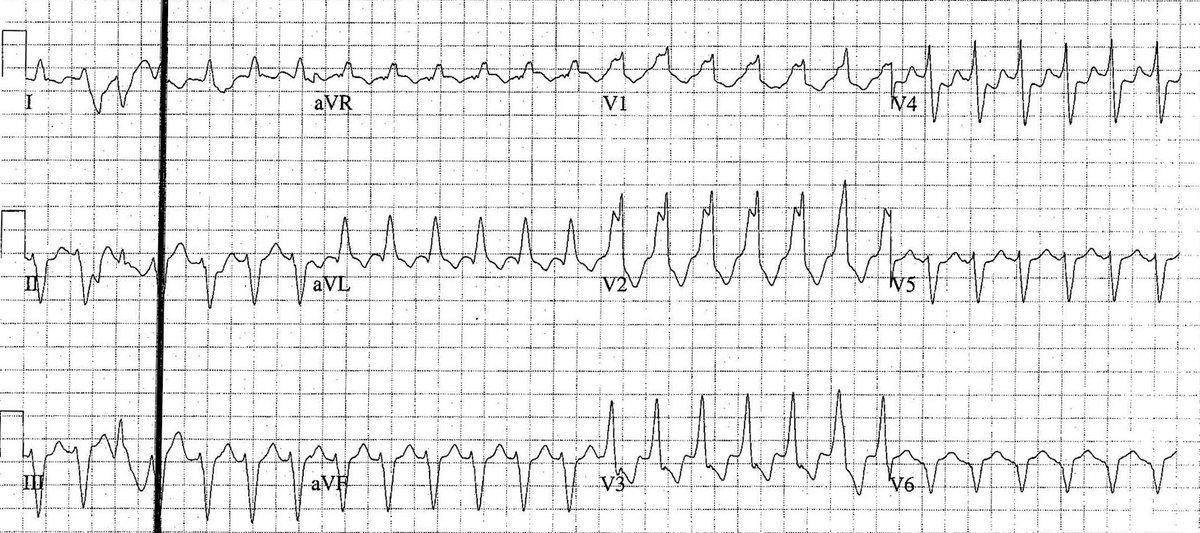

What's going on here? #CardioEd #MedTwitter @ecgandrhythmRoe @DrAkhilX @drsbk7 @Ecgloverr @smithECGBlog @witchdrkochi

What's going on here? #CardioEd #MedTwitter @ecgandrhythmRoe @DrAkhilX @drsbk7 @Ecgloverr @smithECGBlog @witchdrkochi

This ECG is from an 83 y/o male patient who presented with shortness of breath. - What's the rhythm ? #medtwitter #foamed #cardioed

61y, F, DM & HTN, H/O on-off dizziness & tiredness @smithECGblog @DidlakeDW @PendellM @EM_RESUS @DrRazi4 @KostekMilan @makkyecg @FibrilloFlutter @ecgandrhythmRoe @ECG_BUDDY_ARPI #CardioEd #CardioTwitter